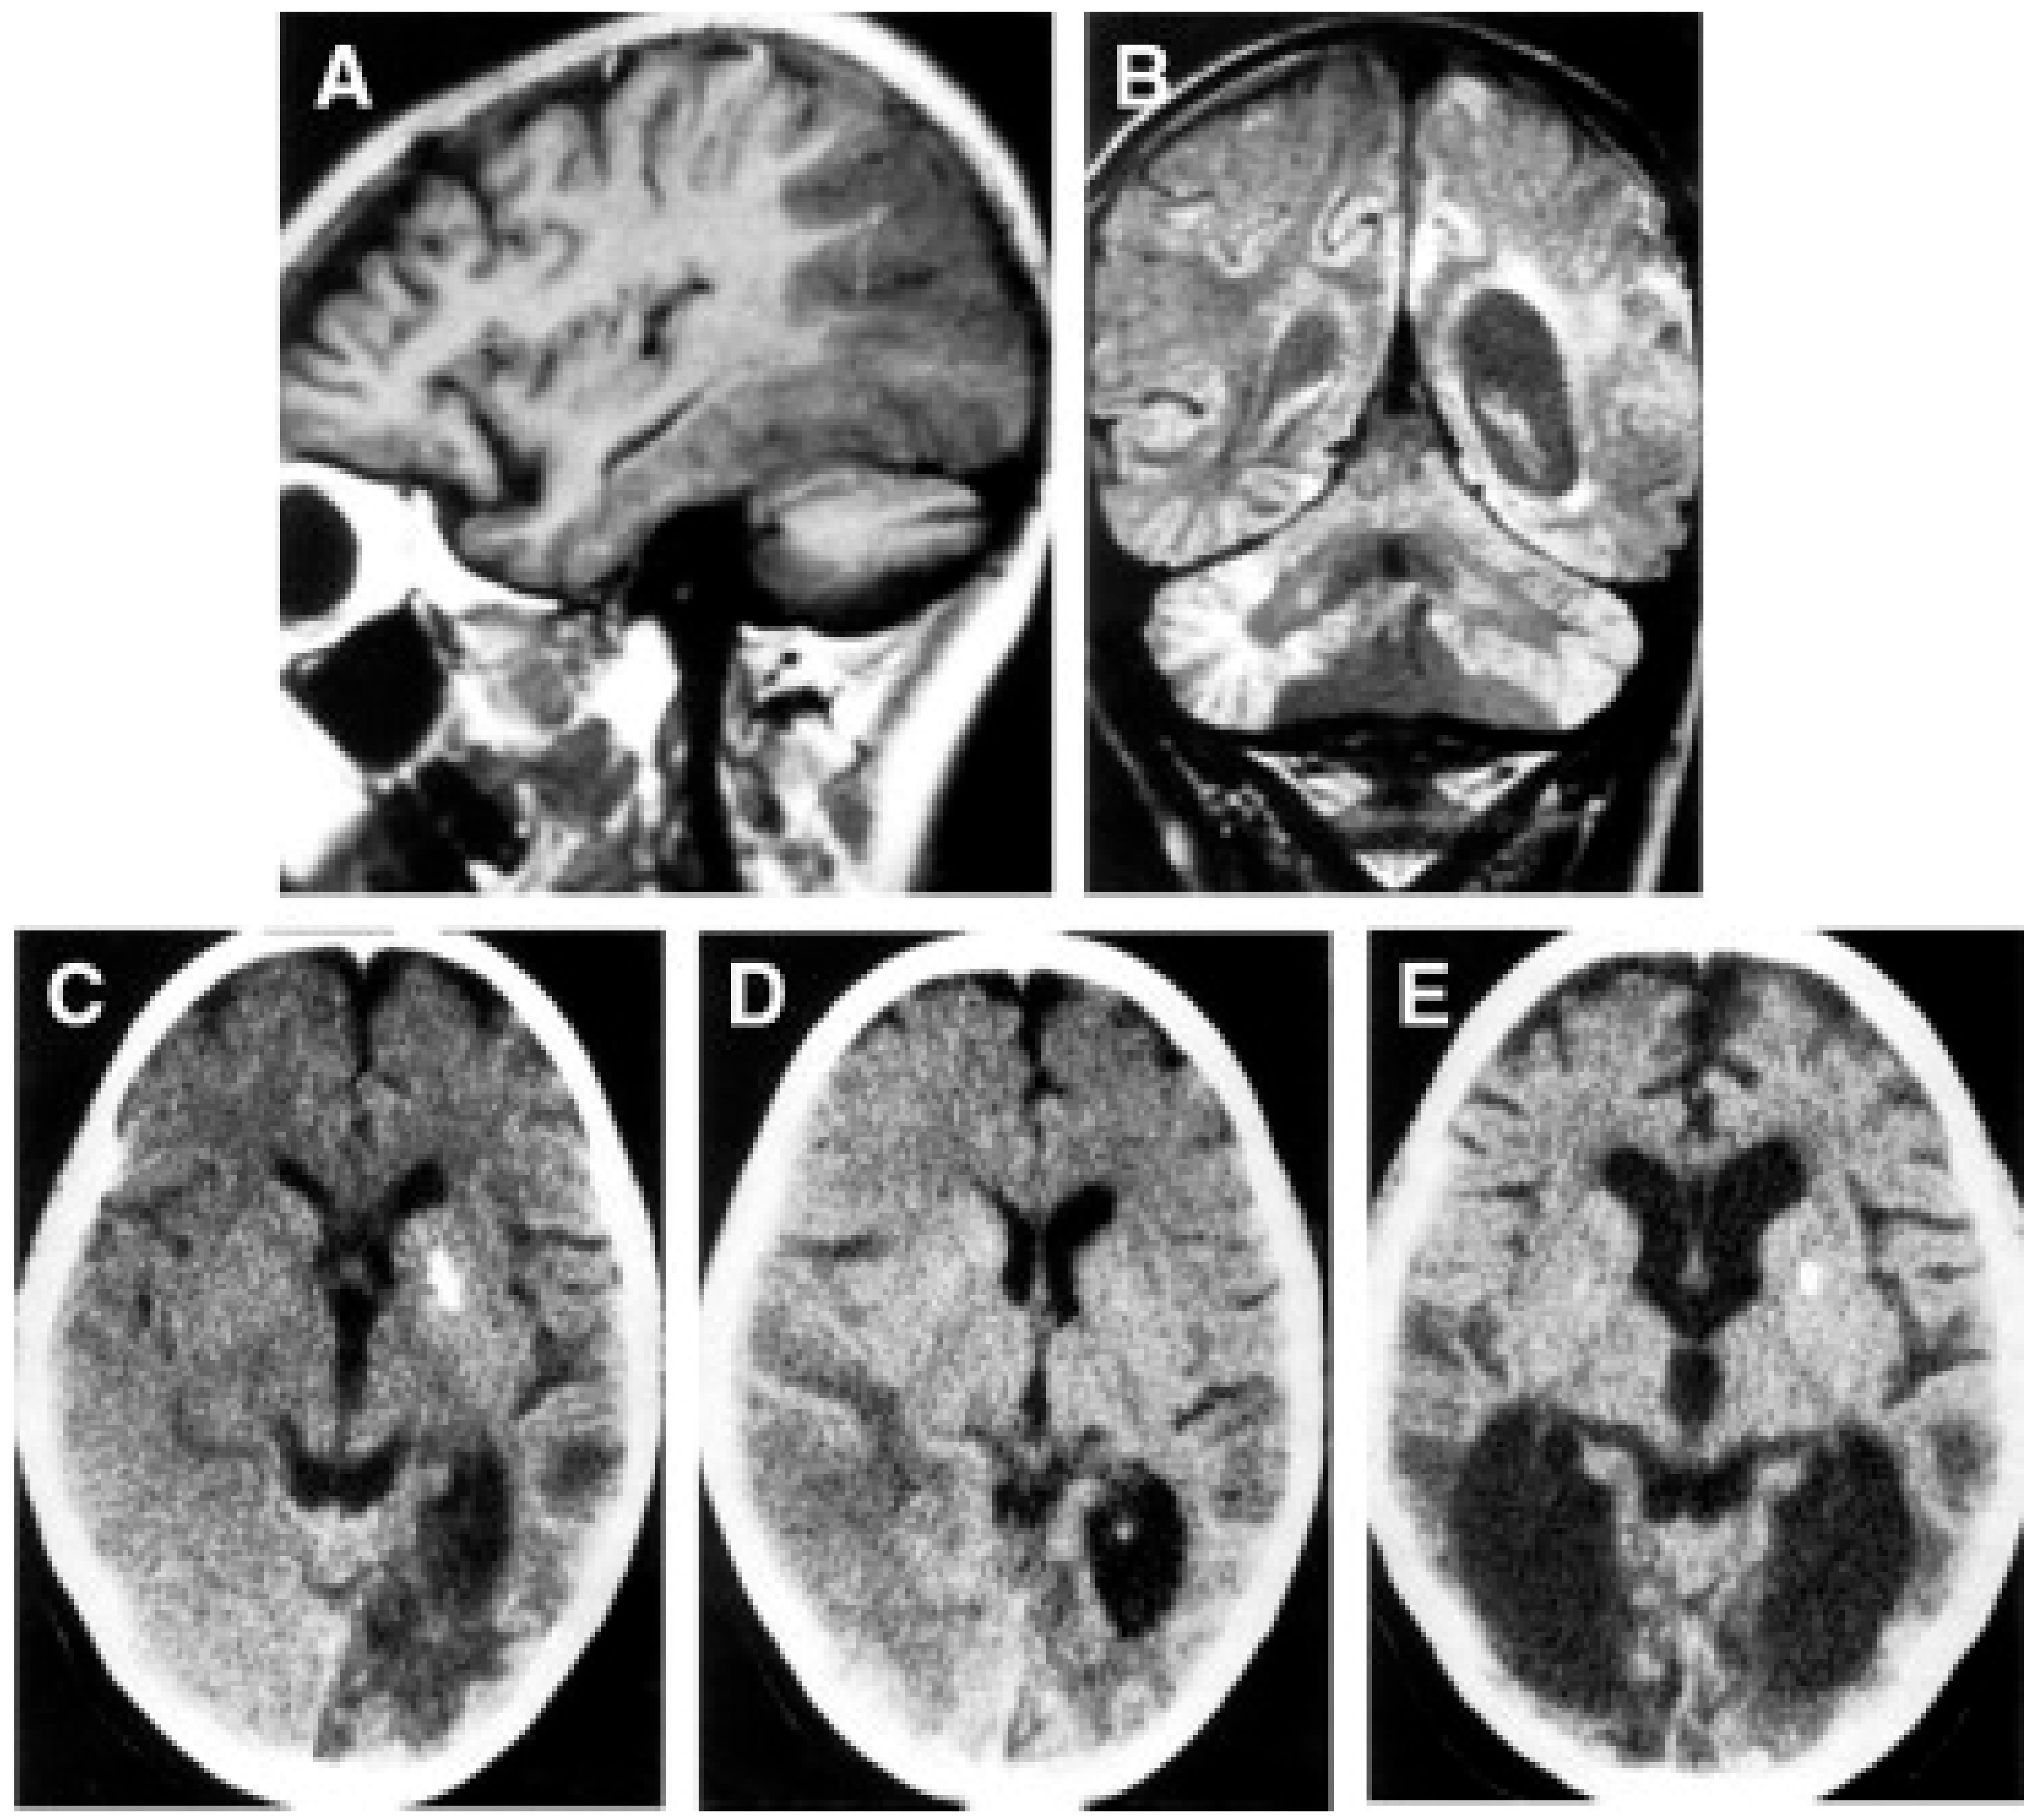

- Savoiardo, M.; Bruzzone, M.G.; D’Incerti, L.; Farina, L.; Grisoli, M. Metabolic and Genetic Diseases of the Brain. Riv. Neuroradiol. 1999, 12, 73–86. [Google Scholar] [CrossRef]

- Mizukami, K.; Sasaki, M.; Suzuki, T.; Shiraishi, H.; Koizumi, J.; Ohkoshi, N.; Ogata, T.; Mori, N.; Ban, S.; Kosaka, K. Central Nervous System Changes in Mitochondrial Encephalomyopathy: Light and Electron Microscopic Study. Acta Neuropathol. 1992, 83, 449–452. [Google Scholar] [CrossRef]

- Tsuchiya, K.; Miyazaki, H.; Akabane, H.; Yamamoto, M.; Kondo, H.; Mizusawa, H.; Ikeda, K. MELAS with Prominent White Matter Gliosis and Atrophy of the Cerebellar Granular Layer: A Clinical, Genetic, and Pathological Study. Acta Neuropathol. 1999, 97, 520–524. [Google Scholar] [CrossRef]